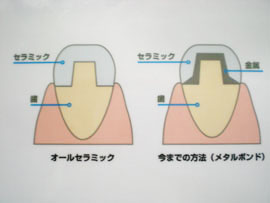

メタルボンドクラウンは虫歯の治療後、歯の表面を削って、薄い金属にセラミックを焼き付けたクラウン(かぶせ物)を取り付ける方法で、従来から最もよく用いられているセラミック修復法です。 自然な歯の色を再現することができ、変色することもありません。

特に、大臼歯やブリッジなど強度を必要とする修復に適しています。